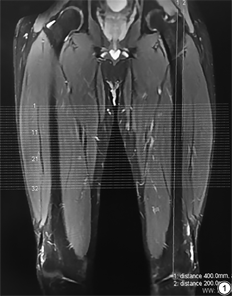

所有志愿者均在GE 3.0 T (Discovery 750W,美国) MR扫描仪上进行左侧大腿中部区域的扫描,采用体部16通道相控阵线圈。线圈中心在大腿中部位置,志愿者双腿并拢,脚尖向上,在受试者左侧小腿部放置泡沫垫以最大限度减少扫描过程中产生的运动伪影。扫描序列包括:轴位:IDEAL-IQ、T1WI FSE;冠状位:T2 IDEAL序列,扫描参数见表1。T2WI冠状位(近端包括双侧股骨头,远端至膝关节)扫描以确认大腿中部位置及排除大腿可能存在的肌肉病变。

将所有大腿MR扫描图像导入GE后处理工作站ADW4.6,在冠状位上确定大腿中部位置对应的轴位T1WI、脂肪分数图的层数(图1),将T1WI及脂肪分数图进行匹配。由住院医师A在T1WI图像上进行ROI的勾画,勾画过程中ROI距离肌肉边缘1~2 mm,避免将皮下及肌间脂肪勾入ROI内。记录每块肌肉的脂肪分数(fat fraction,FF) (图2)。